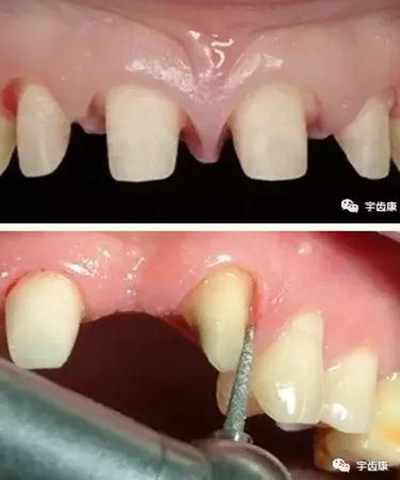

4. 預(yù)留修復(fù)體的空間

5. 邊緣的適合性

牙體各個面的解剖厚度

烤瓷牙結(jié)構(gòu)知識

烤瓷牙的設(shè)計方式